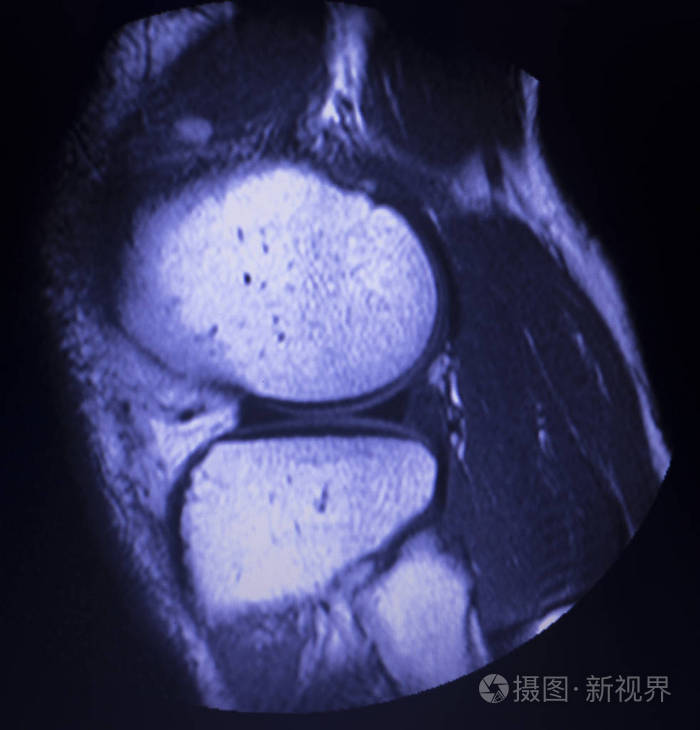

半月板3度撕裂共振图

磁共振成像mri膝后角内侧半月板撕裂最少的结果.照片

图片尺寸375x300

磁共振成像mri膝后角内侧半月板撕裂最少的结果.

图片尺寸700x730